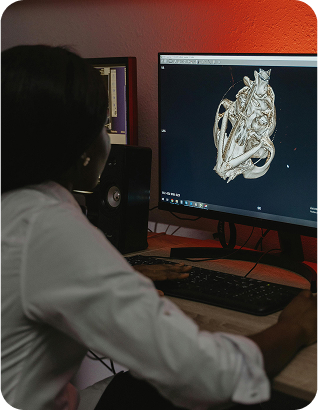

CIMEN acelera el futuro del diagnóstico médico con Perennity

Desafío: Retrasos y dificultades en el acceso y almacenamiento de imágenes médicas, lo que afectaba la eficiencia operativa y la experiencia del paciente.

Solución: Implementación de Perennity Plus en marzo de 2023, plataforma de gestión radiológica que centralizó información, agilizó procesos y mejoró la calidad del diagnóstico.

- Acceso rápido y seguro a imágenes médicas.